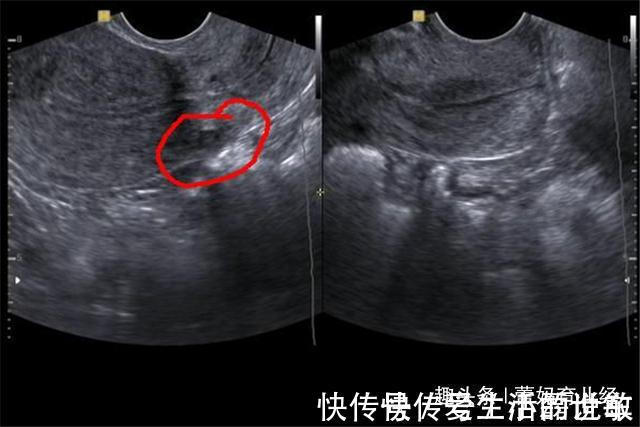

文章插图